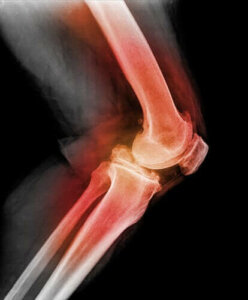

Patellar veya diz kapağı çıkığı tanısı koymak için, doktor patella’ya dokunacak ve dizini farklı yönlerde hareket ettirerek bükecektir. X-ışınları, manyetik rezonans görüntüleme (MRI) veya bilgisayarlı tomografi (BT) kullanarak çıkık diz kapağı ve diğer diz yaralanmalarının görüntülerini görebilirler.